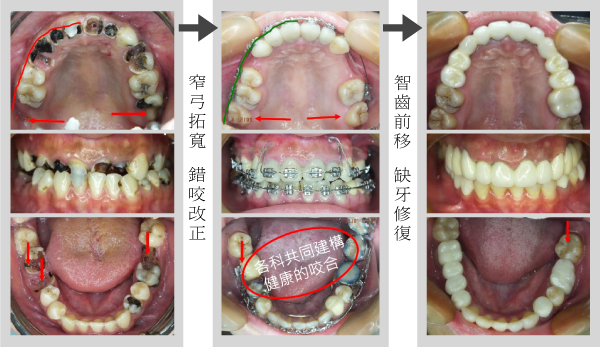

各科都有問題:根管治療、口腔外科、牙周病科、矯正治療、修復治療

案例一

幸福人生從齒起

健齒養顏 開心樂活

天泉專科團隊協同診治 求精求速